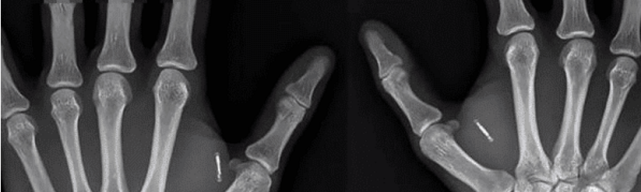

但是功夫不负有心人,只要男子钱出的多,自然会有人接他这笔单子。接他单子的人是一名纹身师,笔者挺好奇的,一个纹身师是哪来的技术将芯片植入体内呢。但是不管怎样,这名纹身师最后也是成功将芯片植入了。

男子在植入完后就兴奋的跑去实验,结果还真有用。他将手背放在门框上,大概用了六秒的时间,车门就打开了。